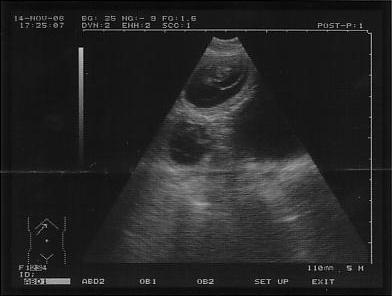

Heute war Abys Ultraschalltermin & es waren auf Anhieb

drei Welpen zu erkennen,

die Ärztin rechnet aber eher mit ca. 5!

Für alle, die etwas erkennen können, hier quasi das erste Foto unseres Kleinen

*g*